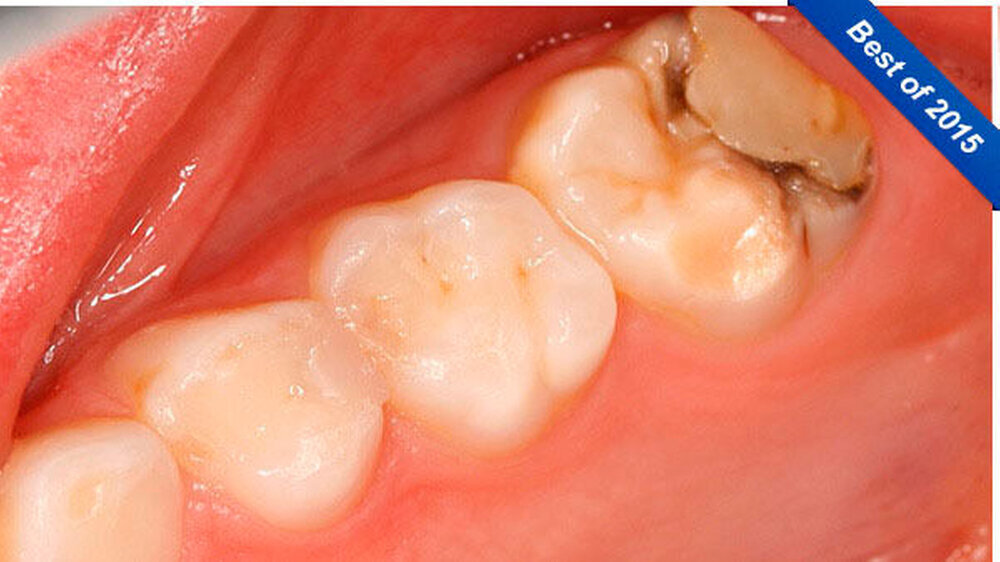

Die Patientin wies ein frühes Wechselgebiss auf, bei dem die Sechsjahr-Molaren, die gesamte Unterkieferfront und die oberen mittleren Inzisivi durchgebrochen waren. Der Zahn 54 hatte eine okklusal-distale Füllung, der Zahn 16 einen okklusal-distal-palatinalen Aufbau (Abbildung 1).

Zusätzlich zeigte der mesio-palatinale Höcker einen deutlichen Schmelzeinbruch (Abbildung 1). Die generelle Mundhygiene war nur mäßig, da insbesondere an den Glattflächen (obere mittlere Inzisivi) auch ohne Anfärbung deutlich sichtbarer Biofilm aufzufinden war (Abbildung 2). Die Zähne 26, 36 und 46 wiesen kaum sichtbare Opazitäten auf, sie waren alle versiegelt (nicht dargestellt).